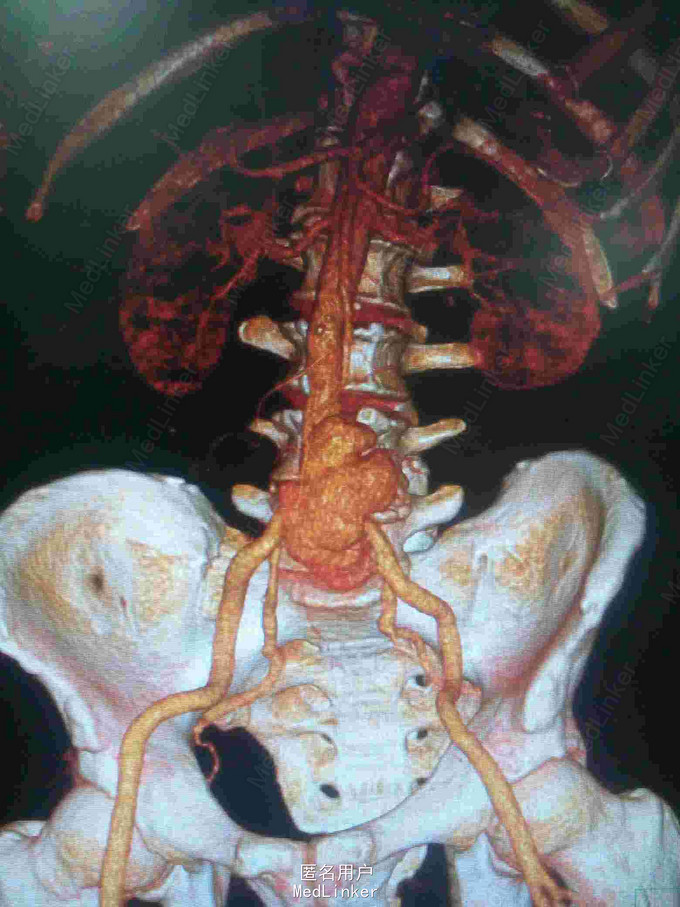

主诉:腰腹痛7月,加重一周。 病史:七月前发热后开始出现腰腹痛,呈持续性撕裂样痛,伴腹胀,症状反复。一周前腹痛症状加重。

体查:下腹部可触及搏动性包块。 辅助检查:腹部CT:腹主动脉假性动脉瘤并血栓形成,腰5椎体受侵蚀。血培养:沙门氏菌。

诊断:沙门氏菌感染性腹主动脉假性动脉瘤 处理:急诊行腹主动脉瘤切除人工血管置换术,术后予美罗培南抗感染8周,续以左氧氟沙星口服。